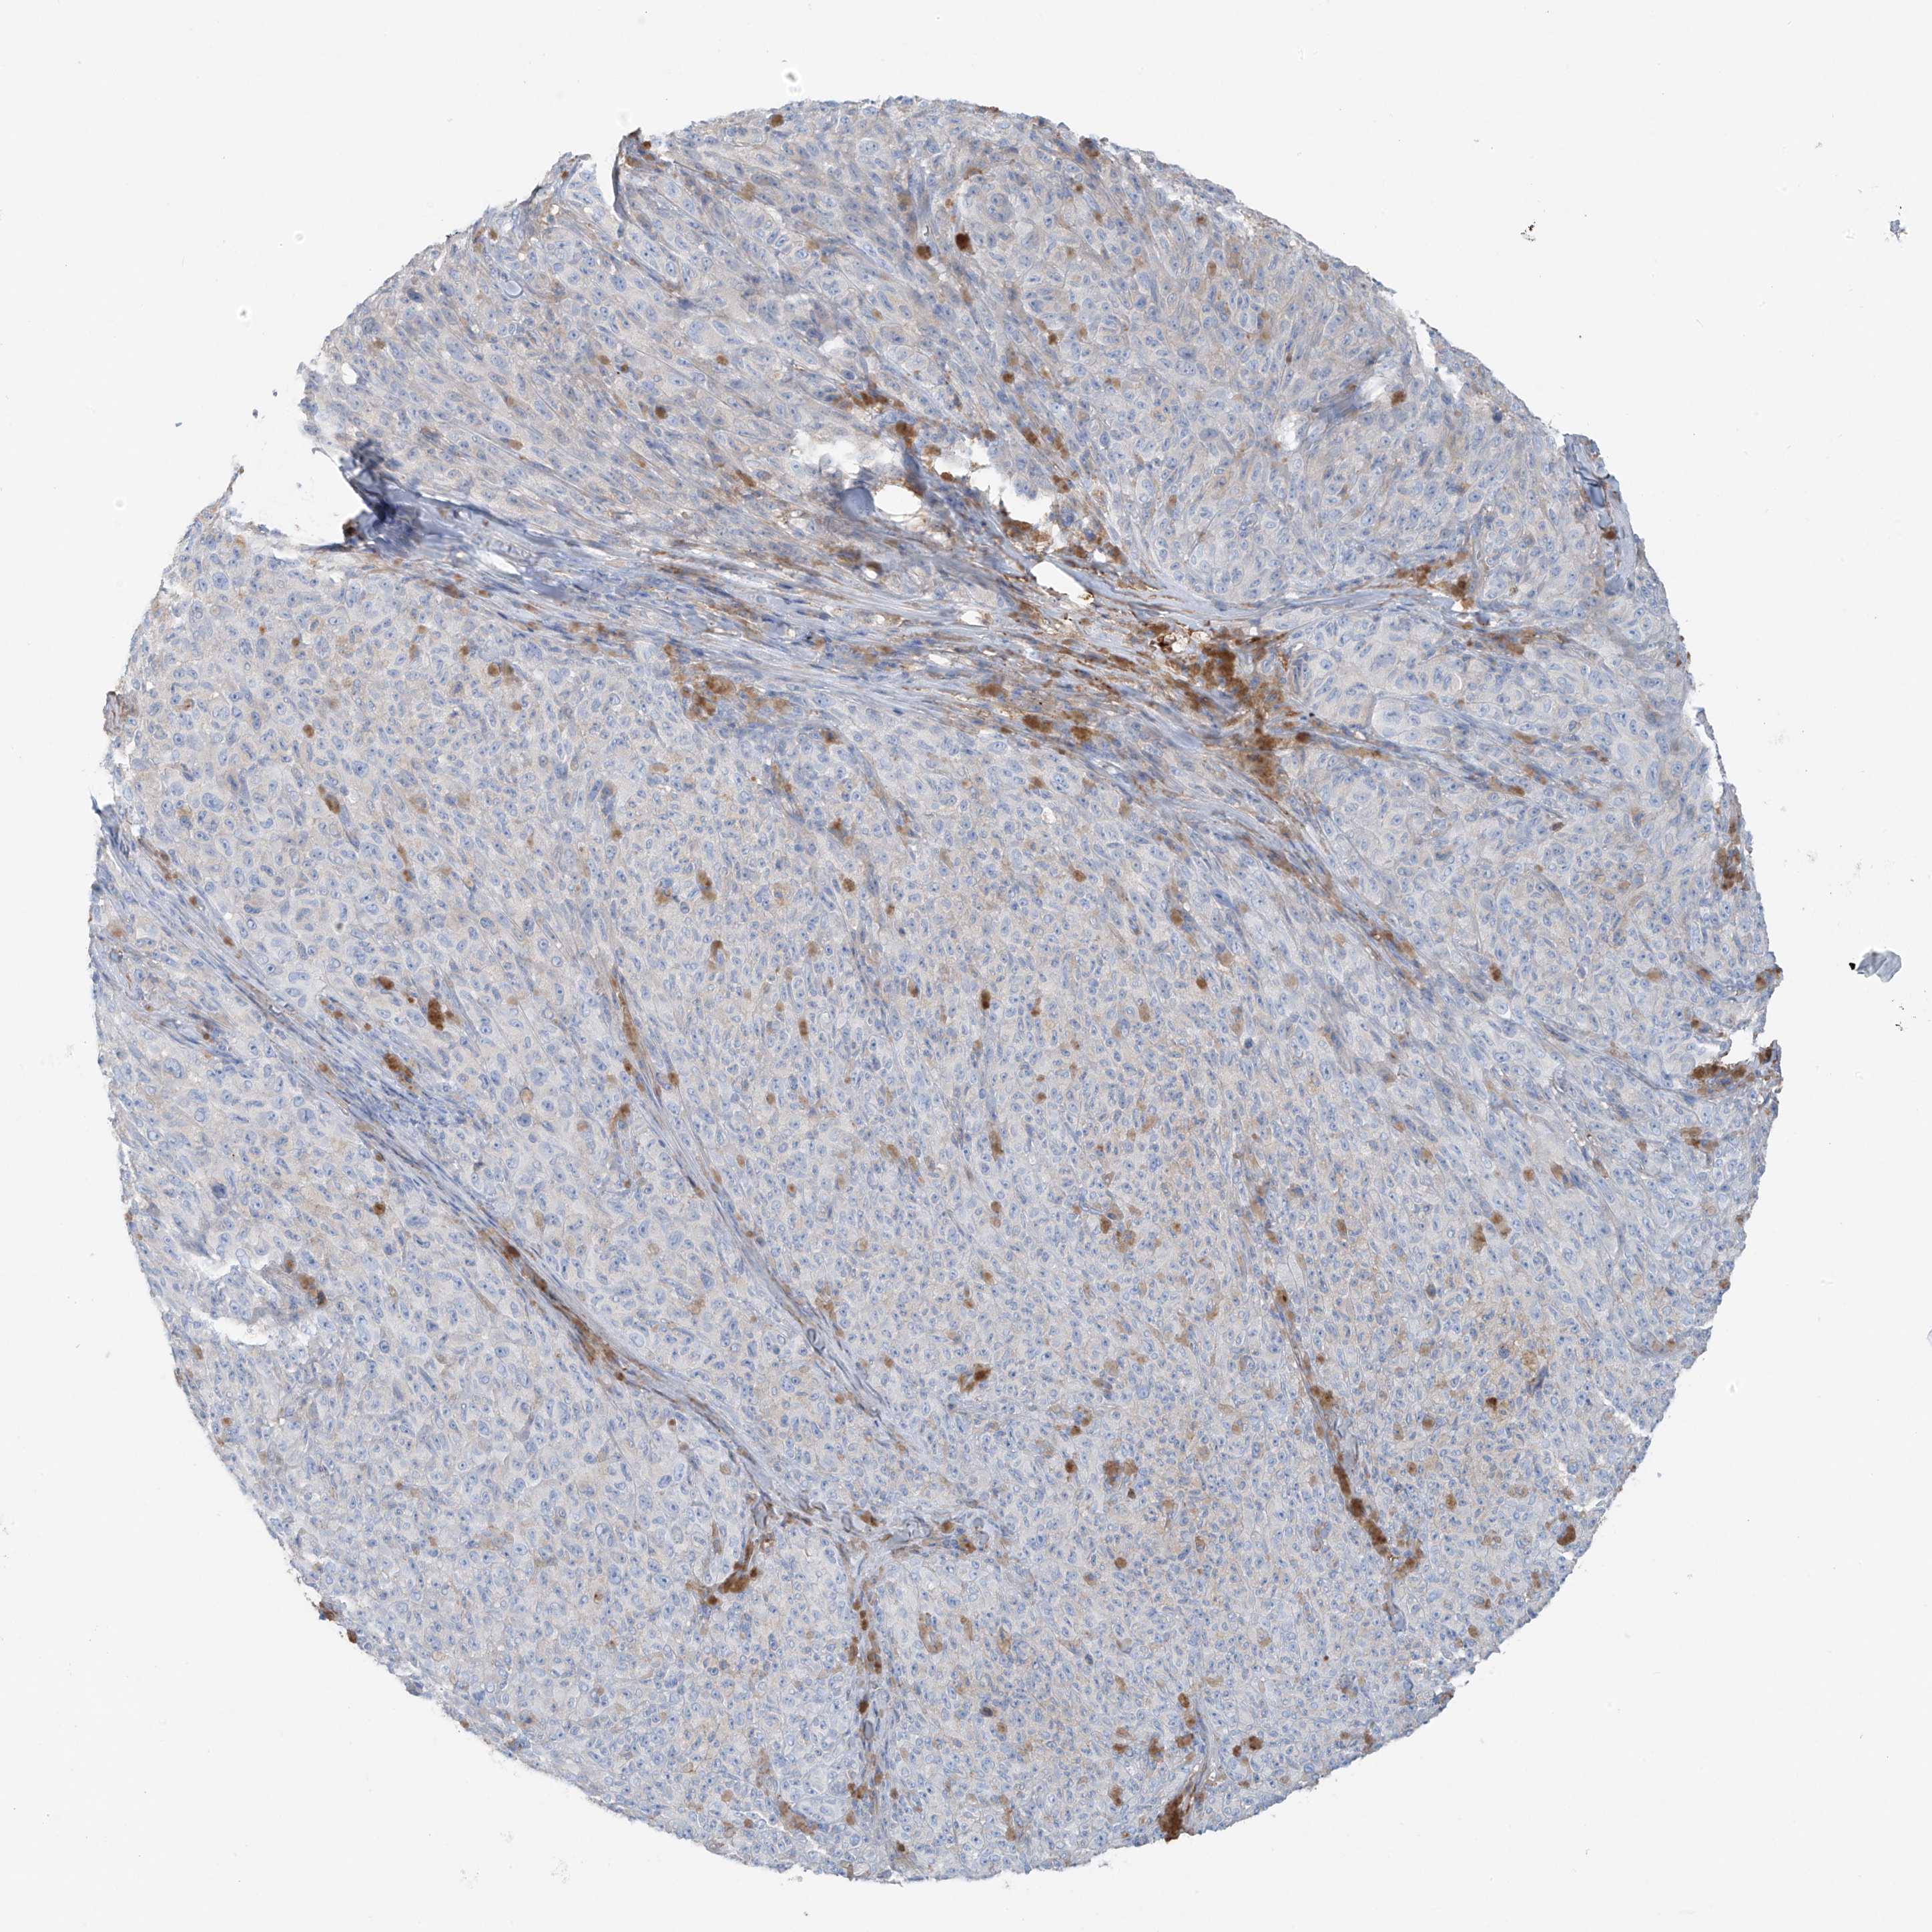

MELANOMA - Protein expressioni

A mouse-over function shows sample information and annotation data. Click on an image to view it in a full screen mode. Samples can be filtered based on level of antibody staining by selecting one or several of the following categories: high, medium, low and not detected. The assay and annotation is described here.

Note that samples used for immunohistochemistry by the Human Protein Atlas do not correspond to samples in the TCGA dataset.

Antibody stainingi

Antibody staining in the annotated cell types in the current human tissue is reported as not detected, low, medium, or high, based on conventional immunohistochemistry profiling in selected tissues. This score is based on the combination of the staining intensity and fraction of stained cells.

Each image is clickable and will lead to virtual microscopy that enables deeper exploration of all samples and also displays staining intensity scores, fraction scores and subcellular localization as well as patient and tissue information for each sample.

Antibody HPA009134

Staining

High

Medium

Low

Not detected

Intensity

Strong

Moderate

Weak

Negative

Quantity

>75%

75%-25%

<25%

None

Location

Nuclear

Cytoplasmic/membranous

Cytoplasmic/membranous,nuclear

Malignant melanoma, NOS

Malignant melanoma, Metastatic site